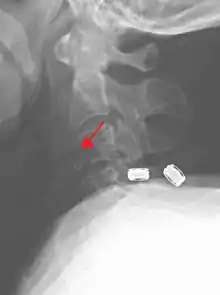

| A fracture of the base of the dens (a part of C2) as seen on CT. | |